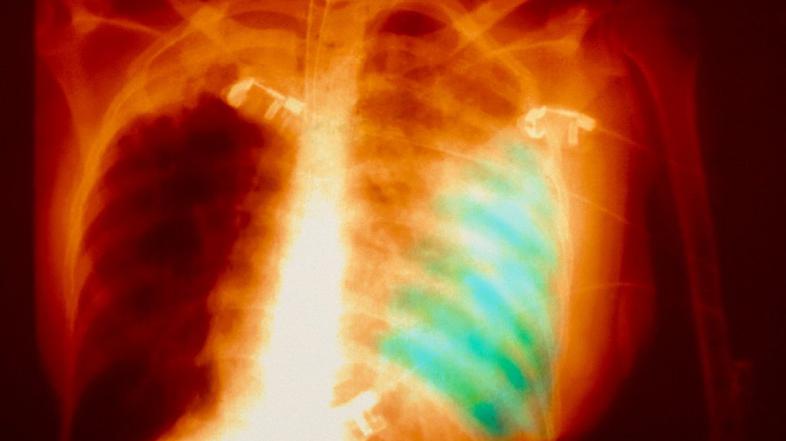

Pljučnica Profimedias

Skrivnostni pljučnici, ki je izbruhnila na Kitajskem, je podlegel tretji bolnik. Bolezen, ki jo povzroča nova vrsta koronavirusa, se medtem širi, prvi primer so zabeležili tudi v Južni Koreji. Na Kitajskem narašča zaskrbljenost, saj se je pljučnica pojavila pred praznovanjem kitajskega novega leta, med katerim bo potovalo na milijone Kitajcev.

Nova vrsta koronavirusa, ki se je najprej pojavila v Wuhanu v osrednjem delu Kitajske, je sprožila preplah, ker izhaja iz iste skupine kot respiratorni virus sars, za katerim je v letih 2002 in 2003 umrlo skoraj 650 ljudi na Kitajskem in v Hongkongu.